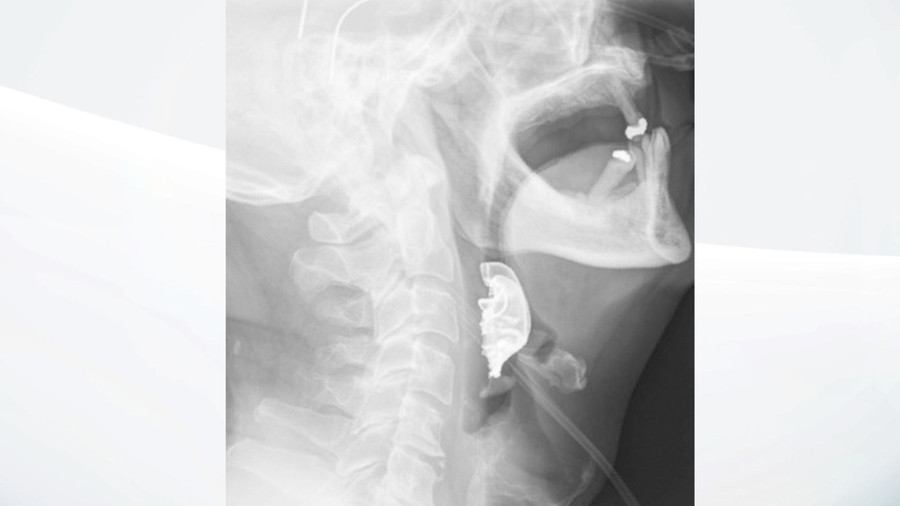

| Hình ảnh hàm răng giả nằm trong thanh quản bệnh nhân |

Tuy nhiên, chỉ 2 ngày sau, tình trạng của người đàn ông ngày một tệ hơn khi không thể nuốt bất kỳ một thứ gì. Sau khi kiểm tra, các bác sĩ đã phát hiện một vật thể hình bán nguyệt nằm ngang thanh quản của người đàn ông, gây sưng tấy bên trong.

Người đàn ông 72 tuổi tiết lộ, răng giả của ông "đã bị mất sau khi nhập viện phẫu thuật” vào 8 ngày trước đó. Ngay sau đó, bệnh nhân đã được tiến hành phẫu thuật khẩn cấp để loại bỏ bộ răng giả và được xuất viện sau 6 ngày.